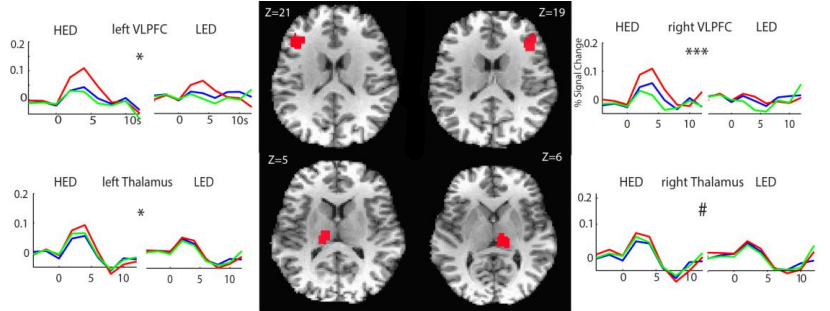

A sample of heavy episodic drinkers (HED) and light episodic drinkers (LD) participated in a color naming Stroop task, where a series of color words were presented in several different font colors. Participants were then required to respond with the color of the font each word was written in. The challenge for this task comes when a color word is written in a different font color (e.g. Red or Blue). In these incongruent conditions, participants have to inhibit the automatic tendency to read the word in order to respond with the font color, which tests cognitive control.

HEDs demonstrated higher levels of activity in the bilateral ventrolateral prefrontal cortex and thalamus during the incongruent condition. These brain regions have been previously implicated in cognitive control, and heightened activation could indicate dysfunction within this system.